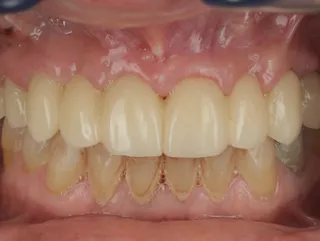

Guided FP1 maxillary rehabilitation with Straumann® STARconcept™ and Straumann iGuide™. A clinical case report by Dr. David Norré, Belgium.

Facially driven Smilecloud design with a focus on preserving tissue and bone. Planned in Smile in a Box and executed with the iGuide protocol; shared pin positions align the drill and prosthetic guides for chairside pickup of the pre-designed provisional. Day-5 follow-up shows the screw-retained provisional in place.

• Day 5 post-op: screw-retained provisional in place.